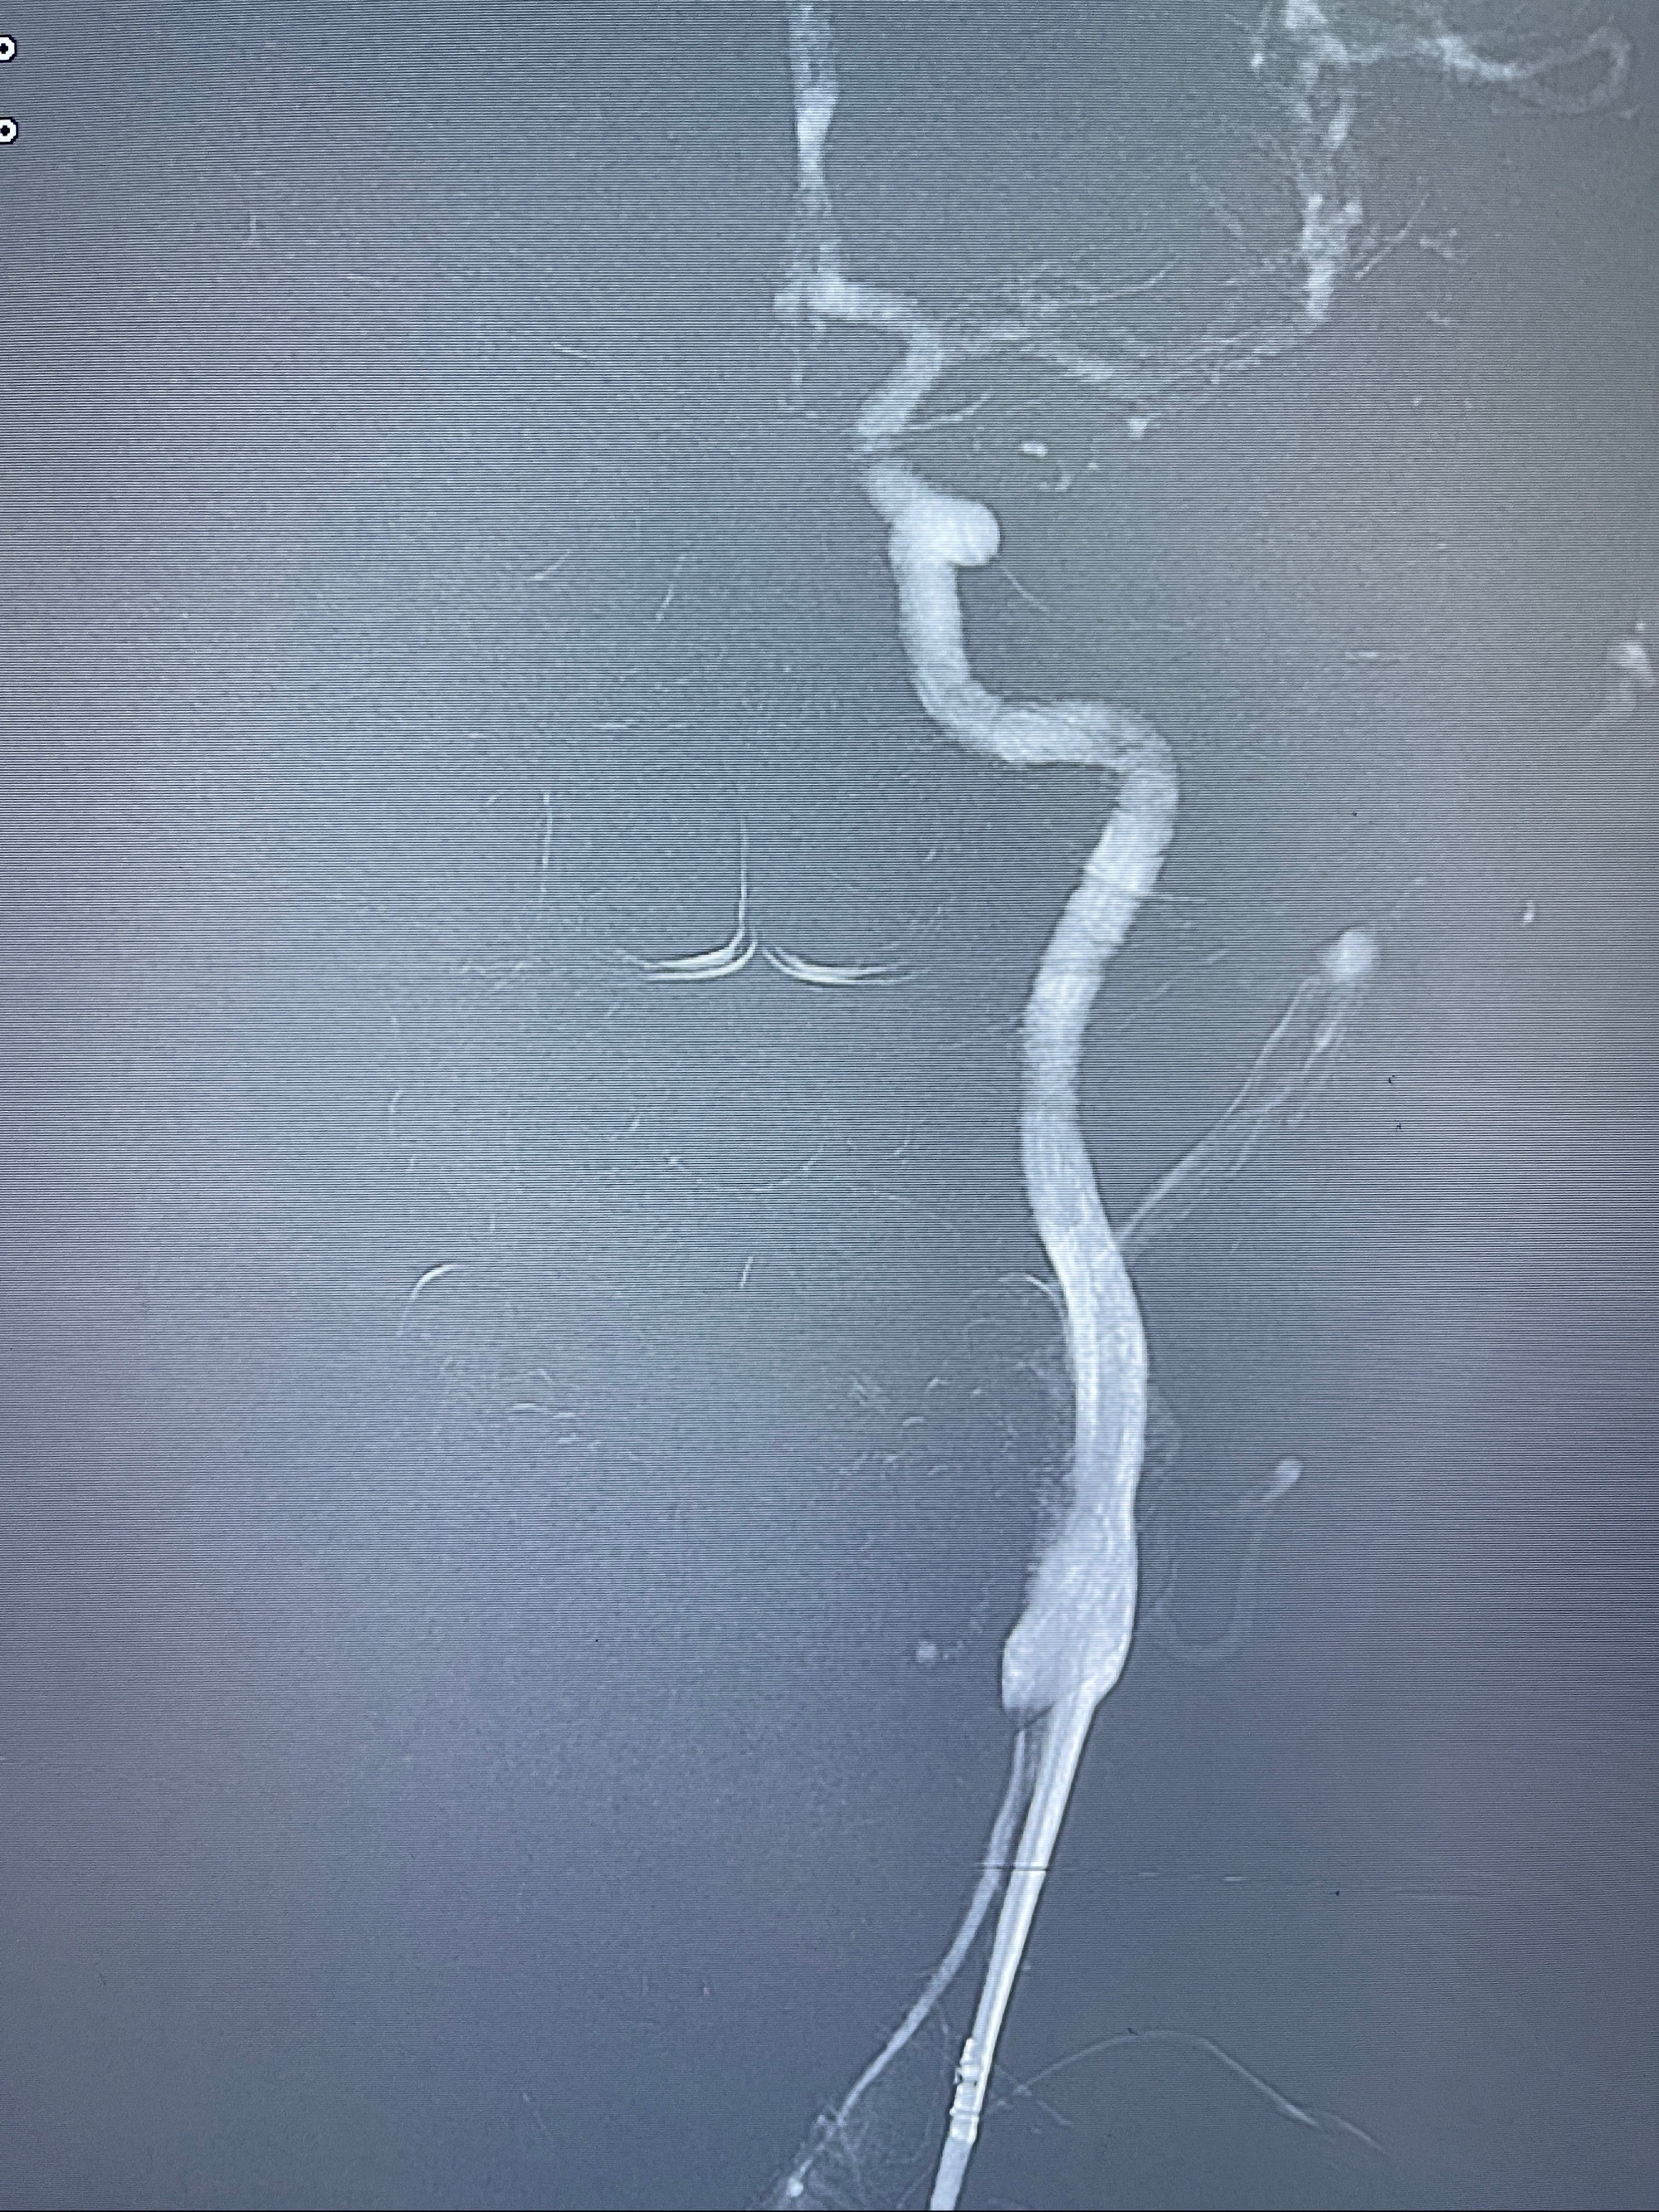

2023-08-14DSA:

左侧大脑中动脉动脉瘤,约2.6-2.8-3.4-2mm大小(瘤颈部、瘤体部、瘤高)